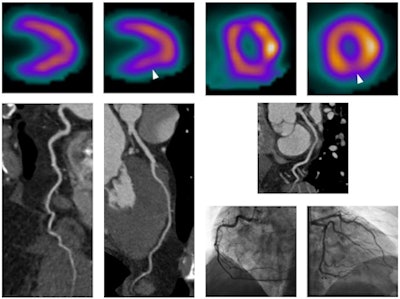

The nuclear tests were performed using a standard stress-rest SPECT protocol with either treadmill (n = 61) or pharmacological (n = 39) stress, Meinel said. Perfusion abnormalities were classified as reversible, fixed, or mixed with transient ischemic dilatation or other abnormalities. After injection of 60 mL to 120 mL of iodinated contrast, CCTA was performed according to standard guidelines using beta-blockers and sublingual nitroglycerin, with electrocardiogram gating or prospective triggering depending on the patient's heart rate and rhythm.

Over the course of the study, the institution transitioned from a 64-detector-row scanner used in 2008-2009 to a dual-source CT used in 2010-2013 (both Siemens Healthcare). The researchers rated coronary vessels as having no luminal narrowing, nonobstructive disease, or potentially obstructive disease, which was defined as 50% stenosis or greater for the study.

At CCTA, 54% of patients had at least one 50% or greater stenosis, while 92% had perfusion abnormalities at SPECT MPI, the authors reported.

At SPECT MPI, most of the perfusion abnormalities were reversible perfusion defects and ischemia, according to Meinel. The fact that only 54% of patients had stenosis indicates "that almost half of patients did not have a potentially obstructive lesion ... and almost one-third of patients had no luminal narrowing at all," he said.

Comparing CCTA with invasive angiography yielded sensitivity of 100% and specificity of 84% for clinically significant CAD, Meinel noted. On a per-patient basis, CCTA delivered a 100% negative predictive value and 83% positive predictive value for clinically significant coronary disease.